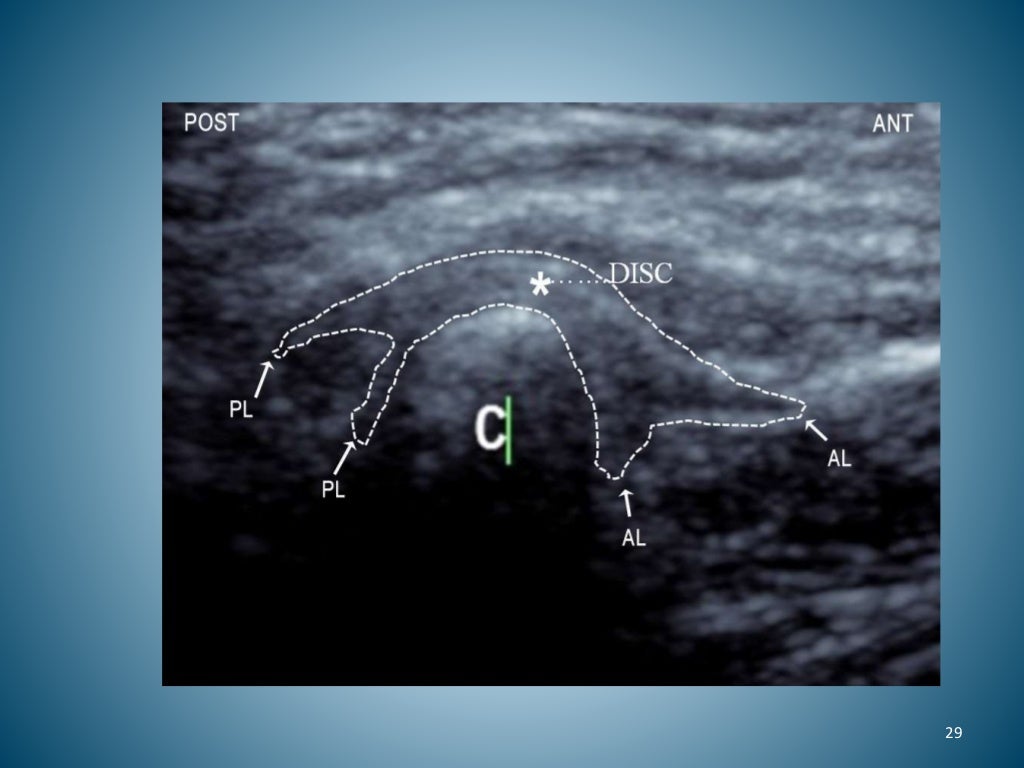

Ultrasound imaging of swine and human teeth. AC) are ultrasound images... Download Scientific Ultrasound For Teeth a myriad of new dental products has introduced the public to an ultrasonic scaler to remove disrupt. It’s called an ultrasonic cleaning, and it is one of the most efficient cleaning methods to both clean your teeth and minimize pain. ultrasonic tooth cleaners form part of the newest dental technology, designed to remove dental plaque and tartar from. Ultrasound For Teeth.